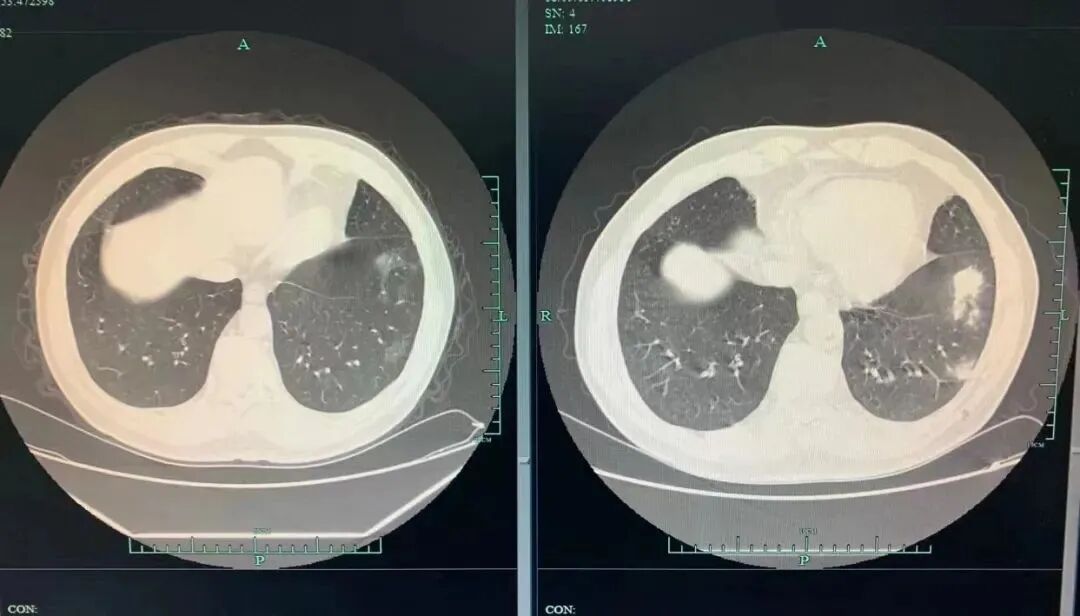

2023年2月,杭州70岁的张大爷(化名)体检时发现肺部有多发结节,于是前往杭州市第一人民医院呼吸与危重症医学科就诊。

医生了解到张大爷常去西湖边喂鸽子后,怀疑是鸽子惹的祸,于是立即安排了气管镜检查。结果显示,病因正是隐球菌。经过3个月的治疗,张大爷的肺结节显著缩小。

3个月前后(图源:杭州日报)